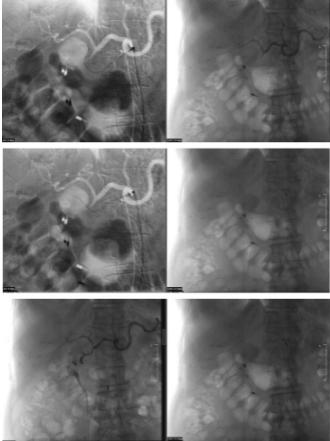

考虑到患者血流动力学的稳定性,尝试血管内治疗。急诊选择性动脉造影腹腔三脚架和超选择性动脉造影肝动脉和胃十二指肠动脉。使用2.9 Fr微导管超选择性置管传入和传出血管,并使用两个5mm×15 mm控释线圈栓塞传出血管。分别用7×29 mm、5×24 mm和4×29 mm线圈栓塞进血管。栓塞后,假性动脉瘤的供应缺失和栓塞道血管的关闭被证实。

发现肝总动脉线圈部分移位。然而,肝总动脉造影显示通畅,可见小的混浊缺损(图3)。

图3、紧急选择性动脉造影